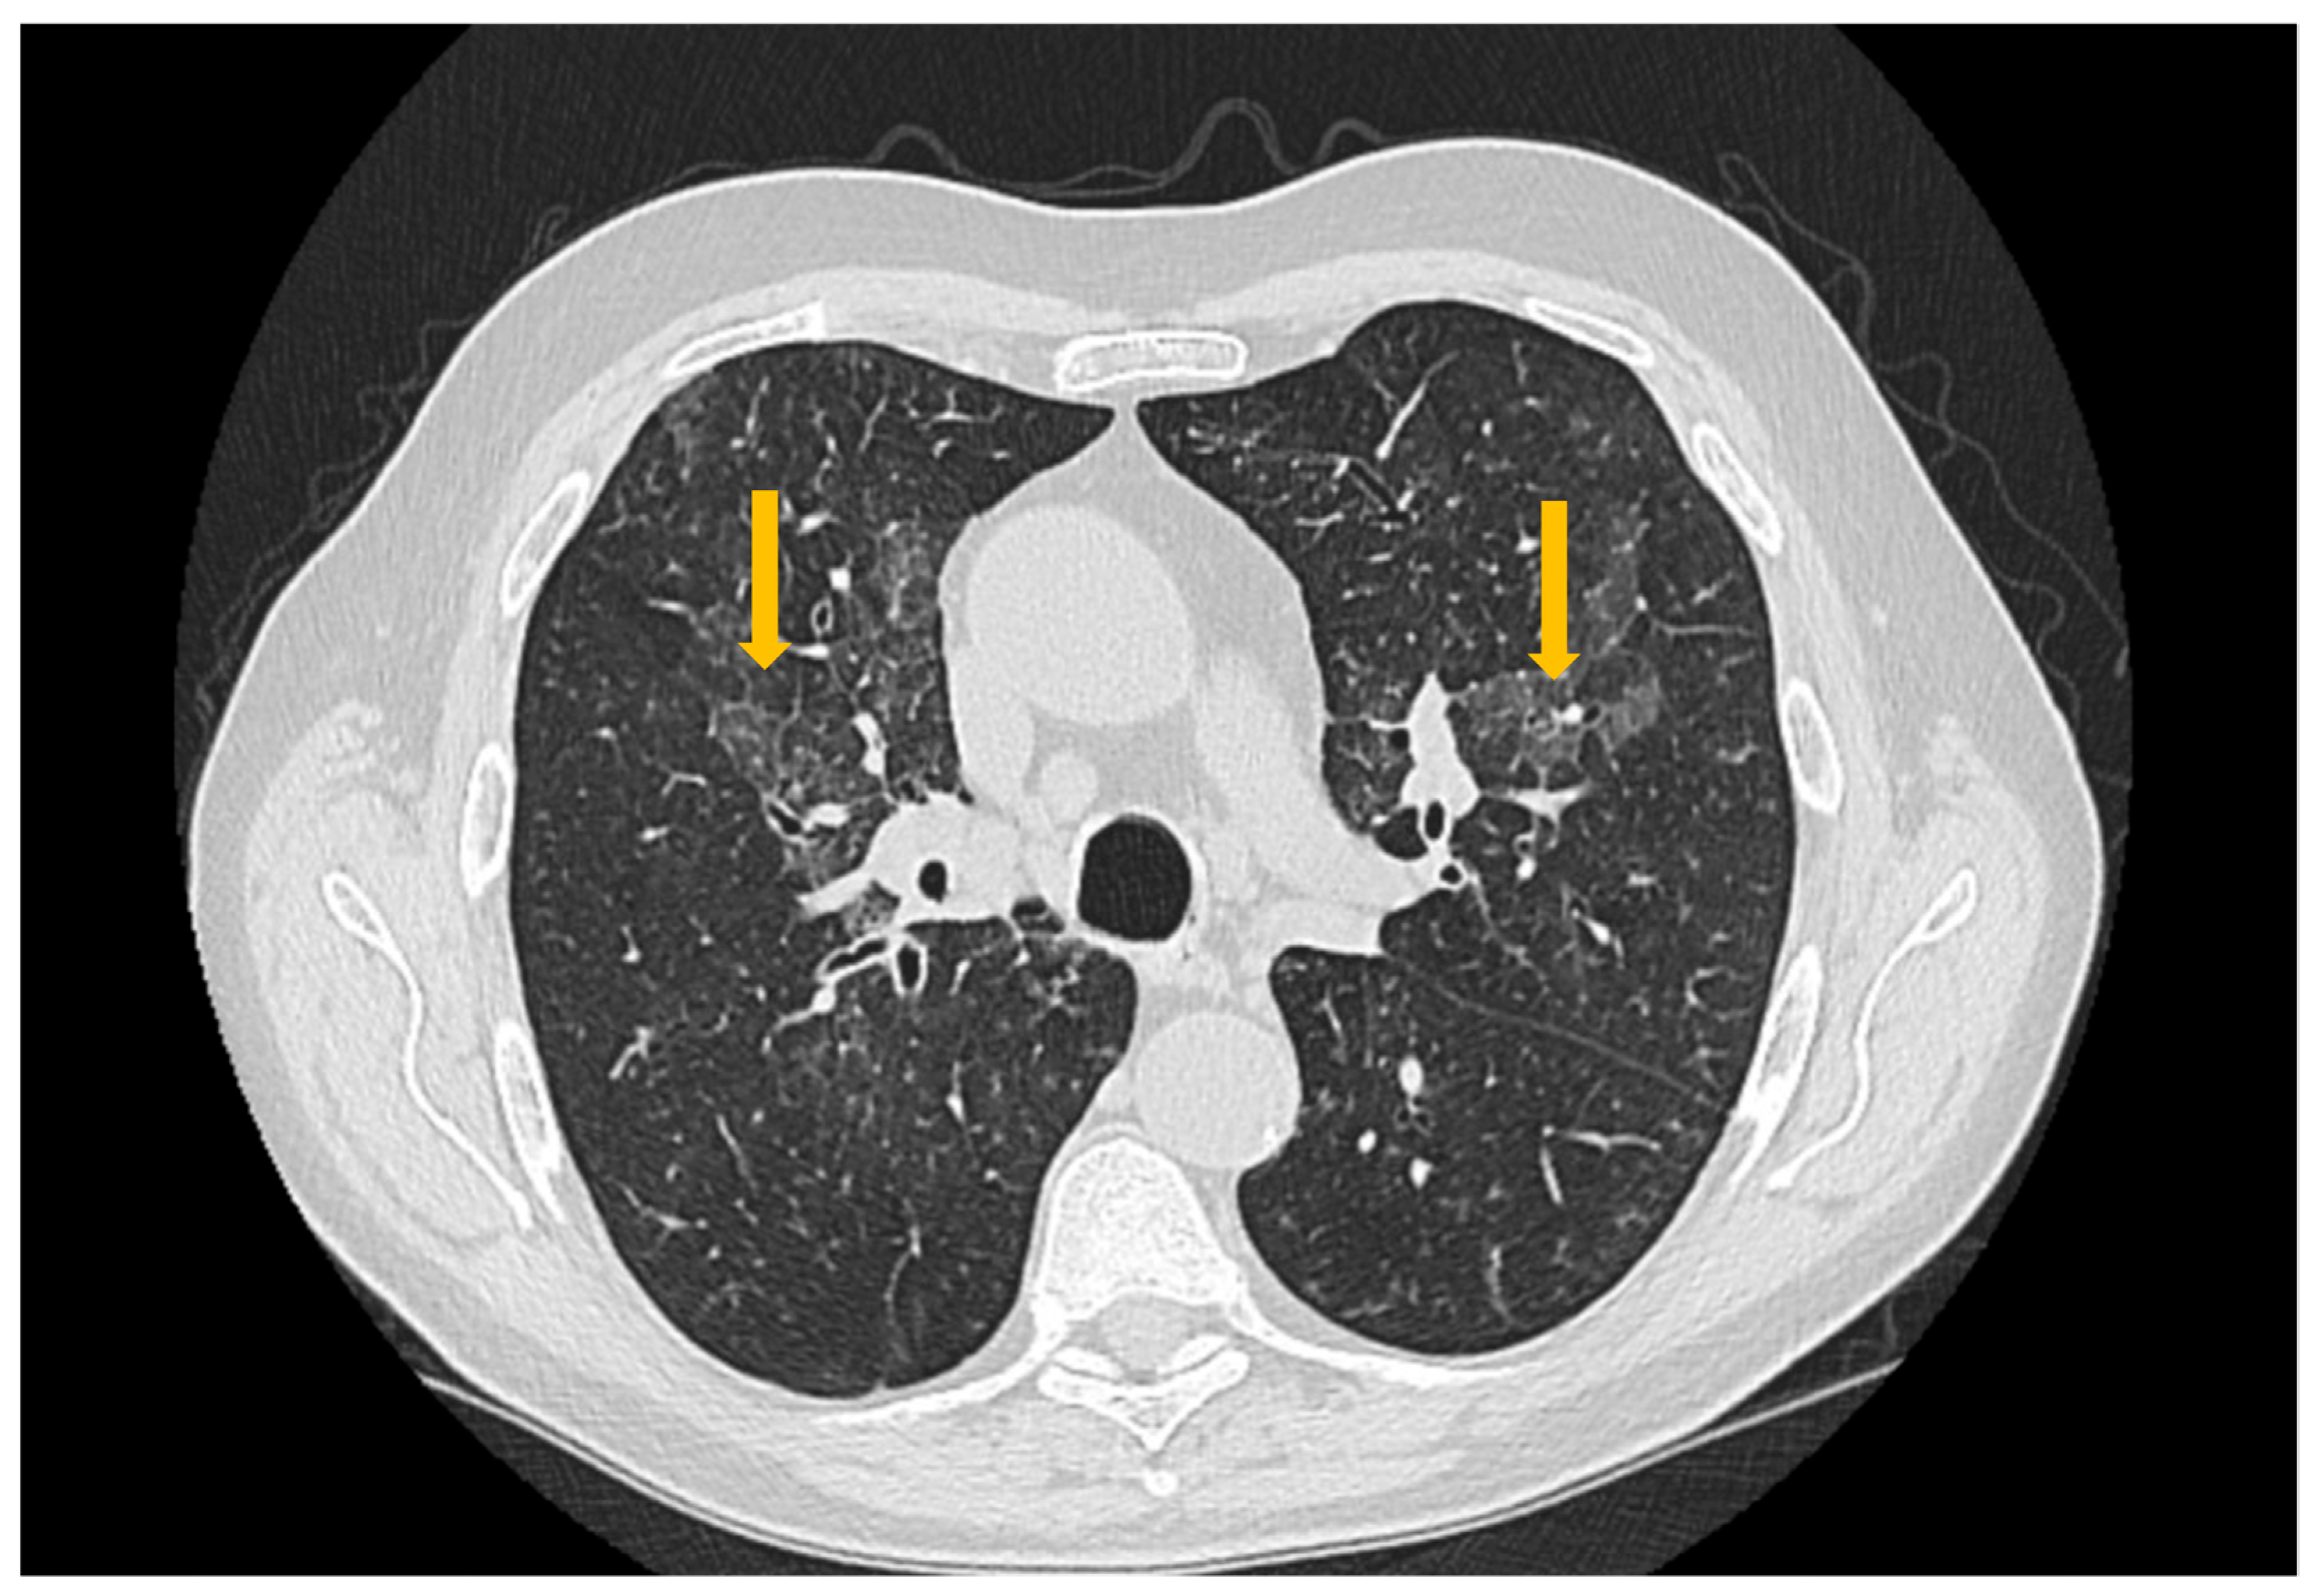

Pulmonary involvement in patients with Sjögren’s syndrome manifests with symptoms such as persistent cough and dyspnea, associated with abnormal findings on diagnostic tests (pulmonary function tests and high-resolution computed tomography—HRCT) [37]. Pulmonary manifestations result from diffuse interstitial pathologies that develop in these patients, the most frequent histologic subtype being non-specific interstitial pneumonia (NSIP) [47], followed by usual interstitial pneumonia (UIP), lymphoid interstitial pneumonia (LIP), and organizing pneumonia (OP) [24]. The prevalence of interstitial lung disease among patients with Sjögren’s syndrome is 23% [24].

High-resolution computed tomography represents the gold standard for evaluating pulmonary changes in diffuse interstitial lung diseases [48]. This imaging technique has a sensitivity of 100%, specificity of 82%, positive predictive value of 97%, and negative predictive value of 100% for the diagnosis of diffuse interstitial disease [49]. The imaging features vary according to the histologic subtype of involvement (Figure 3, Figure 4 and Figure 5) [50].

Figure 3. High-resolution computed tomography (HRCT) of the chest in non-specific interstitial pneumonia (NSIP). Axial HRCT image demonstrates bilateral, diffuse ground-glass opacities (arrows), associated with interlobular septal thickening and traction bronchiectasis, findings characteristic of fibrotic NSIP.